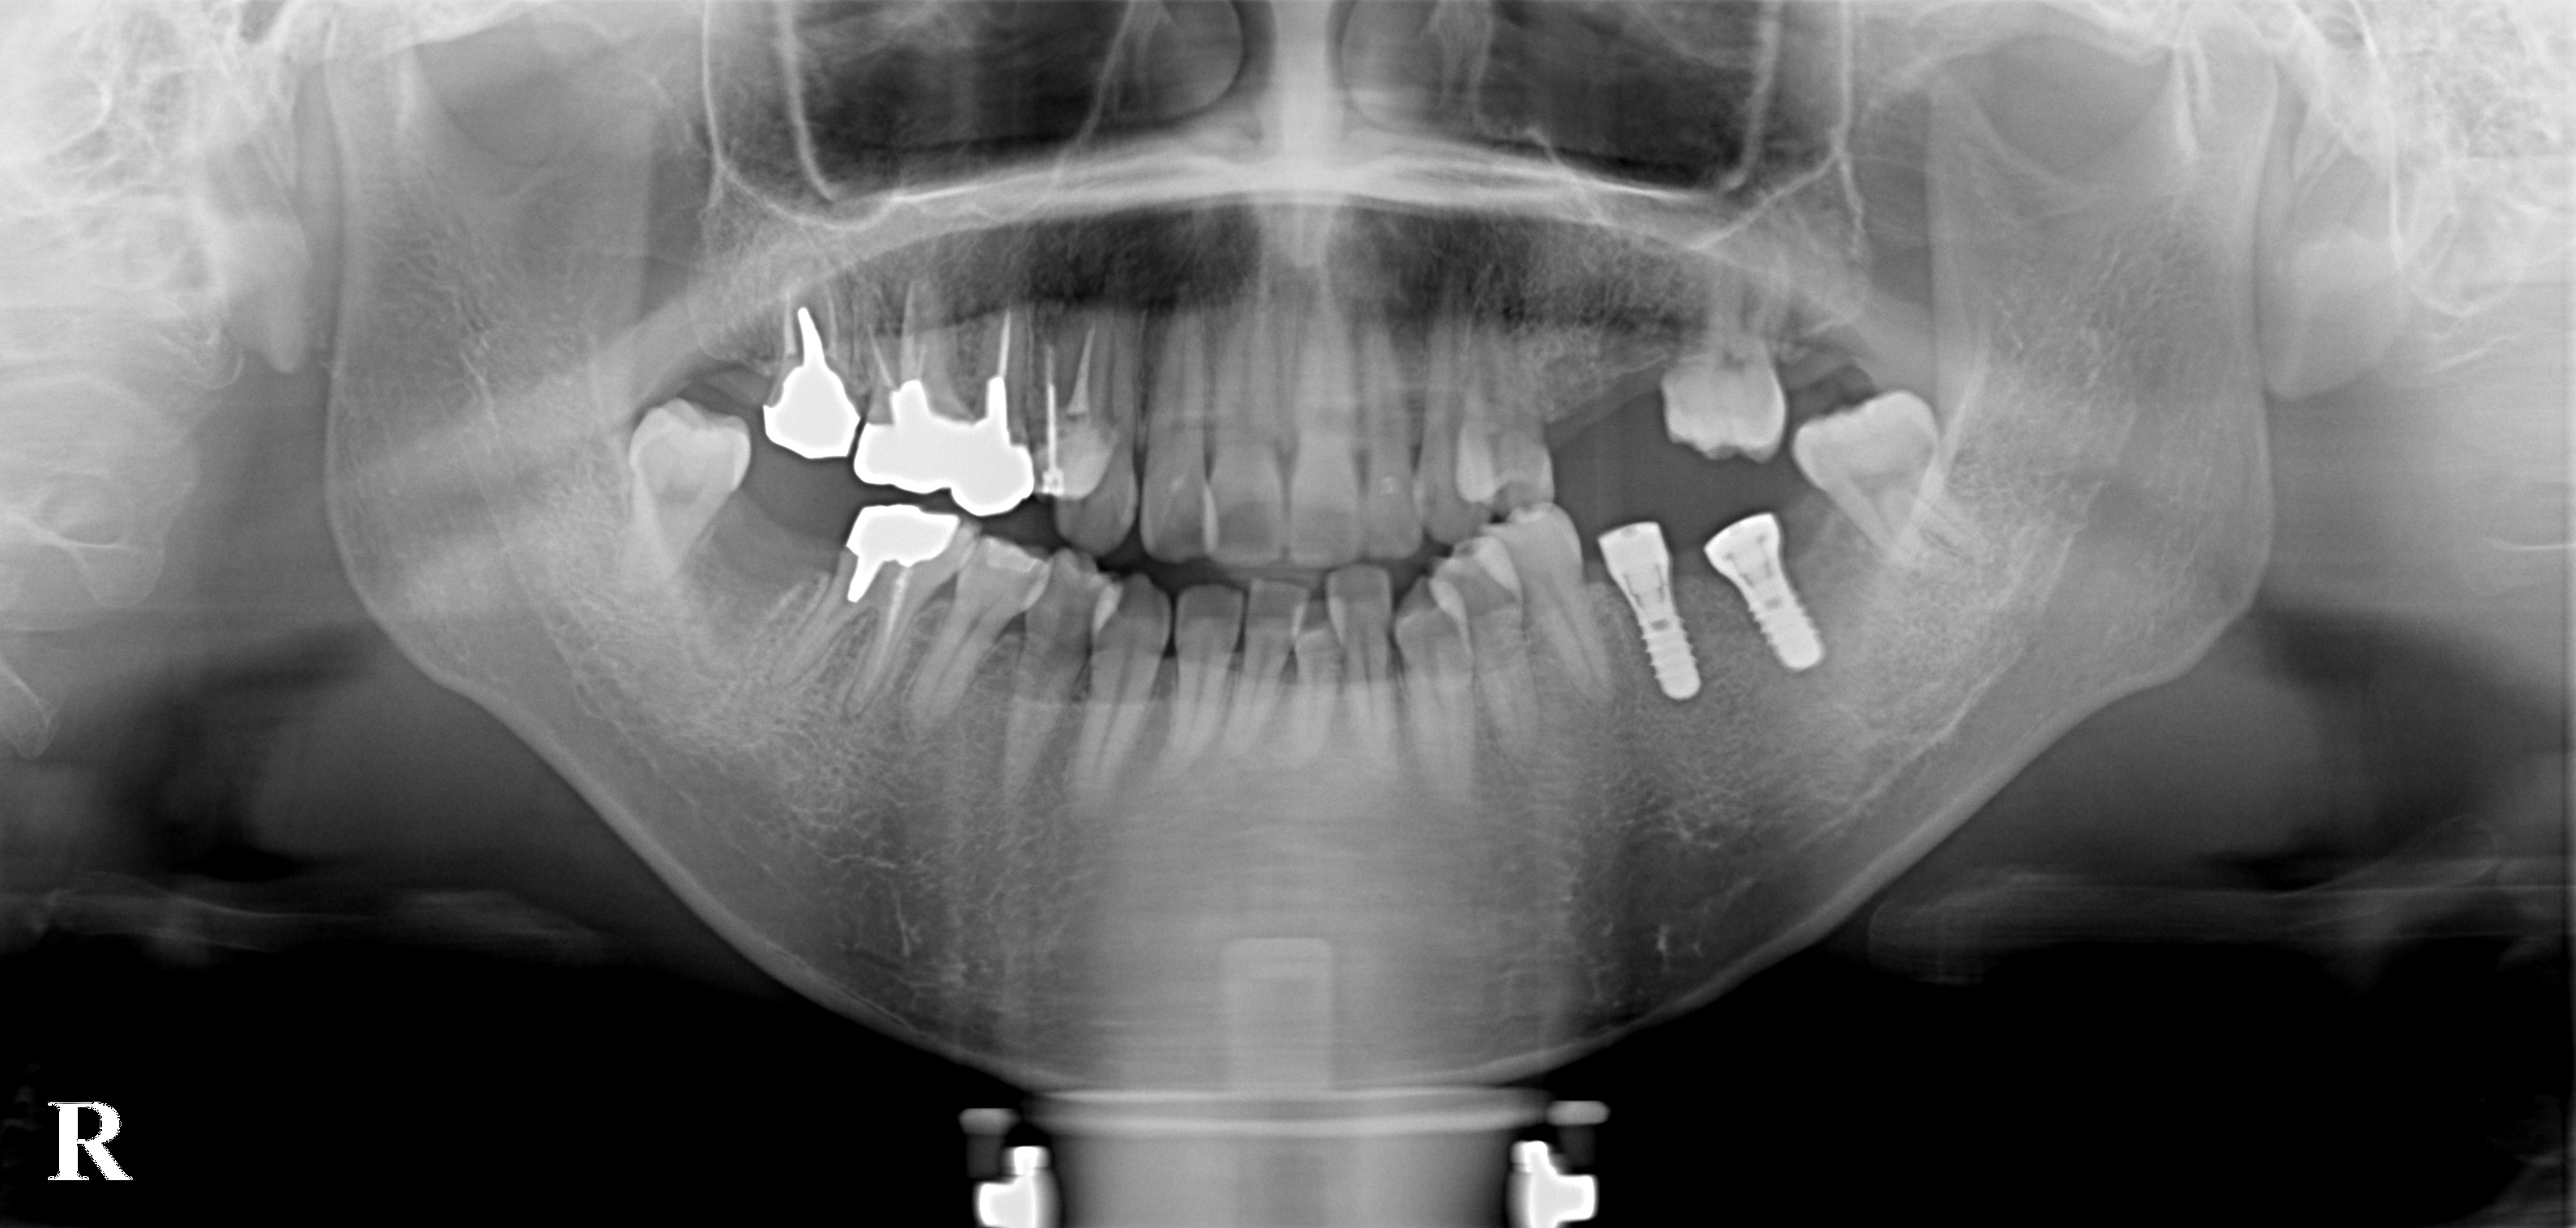

2012年10月 4日 大臼歯インプラント 20代女性

本日は、20代女性の方の奥歯のインプラントを行いました。奥歯がないために食べるのに非常に時間がかかるということでした。CTレントゲンでも骨が十分にありましたので、一番奥のインプラントは、体積が大きいワイドネックのインプラントを使用しました。ほぼ、理想的な場所に入っています。

治療前